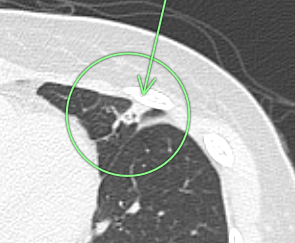

(検診例2)

右肺の上方に1.5cm大の白い結節(○枠+矢印)が指摘されました。

胸部CTの3D画像で、右第2肋骨の骨折治癒像(○枠+矢印)であることが確定しました。